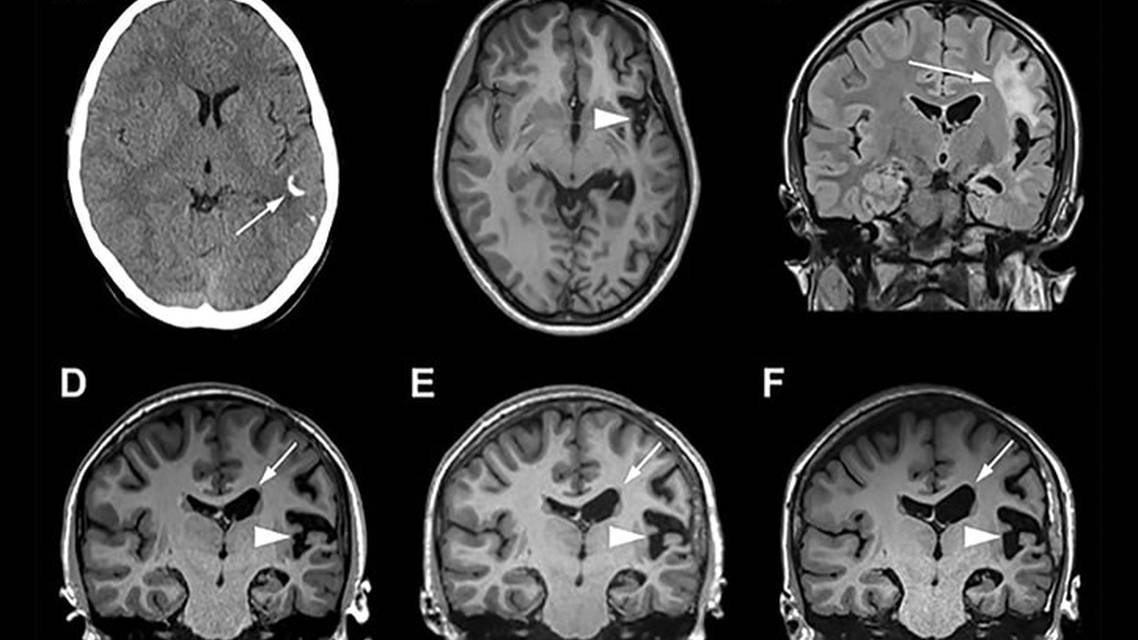

Brain MRI findings are typically ipsilateral to the hemifacial atrophy, although they can be bilateral. The most common imaging findings include white matter hypodensities on CT scans with corresponding T2 or fluid-attenuated inversion recovery (FLAIR) white matter hyperintensities.4,15-16 Intracranial calcifications, predominantly in the frontal lobe, are commonly seen on CT.15-16 Focal or unilateral atrophy is also commonly observed, typically ipsilateral to the cutaneous manifestations.15-17 Other MRI findings include cortical thickening with associated meningeal enhancement, ipsilateral hemorrhages, and cavernous malformations.18 Radiographic findings may be progressive but typically do not progress at the same rate as cutaneous manifestations. 18-19 Histologic findings in PRS may include atrophy of multiple skin layers, including the epidermis, dermis, subcutaneous tissue, and hair follicles.2 There is often associated inflammatory lymphocytic infiltrate, as seen in the case presented here.2